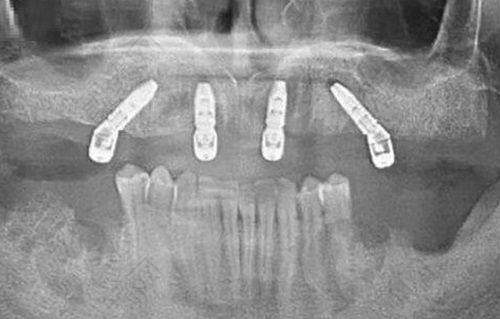

口腔种植科有即刻种植、微创种植、数字化种植等项目。对于牙齿缺失的患者来说,这些种植方式可以根据自身情况进行选择,帮助他们修复牙齿的功能和美观。

洛阳九龙口腔门诊部(周山店)有着不错的口碑。有不少体验日记可以证明这一点,比如看周山路郑淑敏院长的半口种牙病例可以了解种植牙技术;九龙口腔员工钢牙套中途换隐适美隐形矫正改善了下巴后缩的问题;还有人分享了在九龙口腔半隐形陶瓷托槽矫正的30岁正畸经验。这些真实的实例让更多的人对门诊部有了信心。